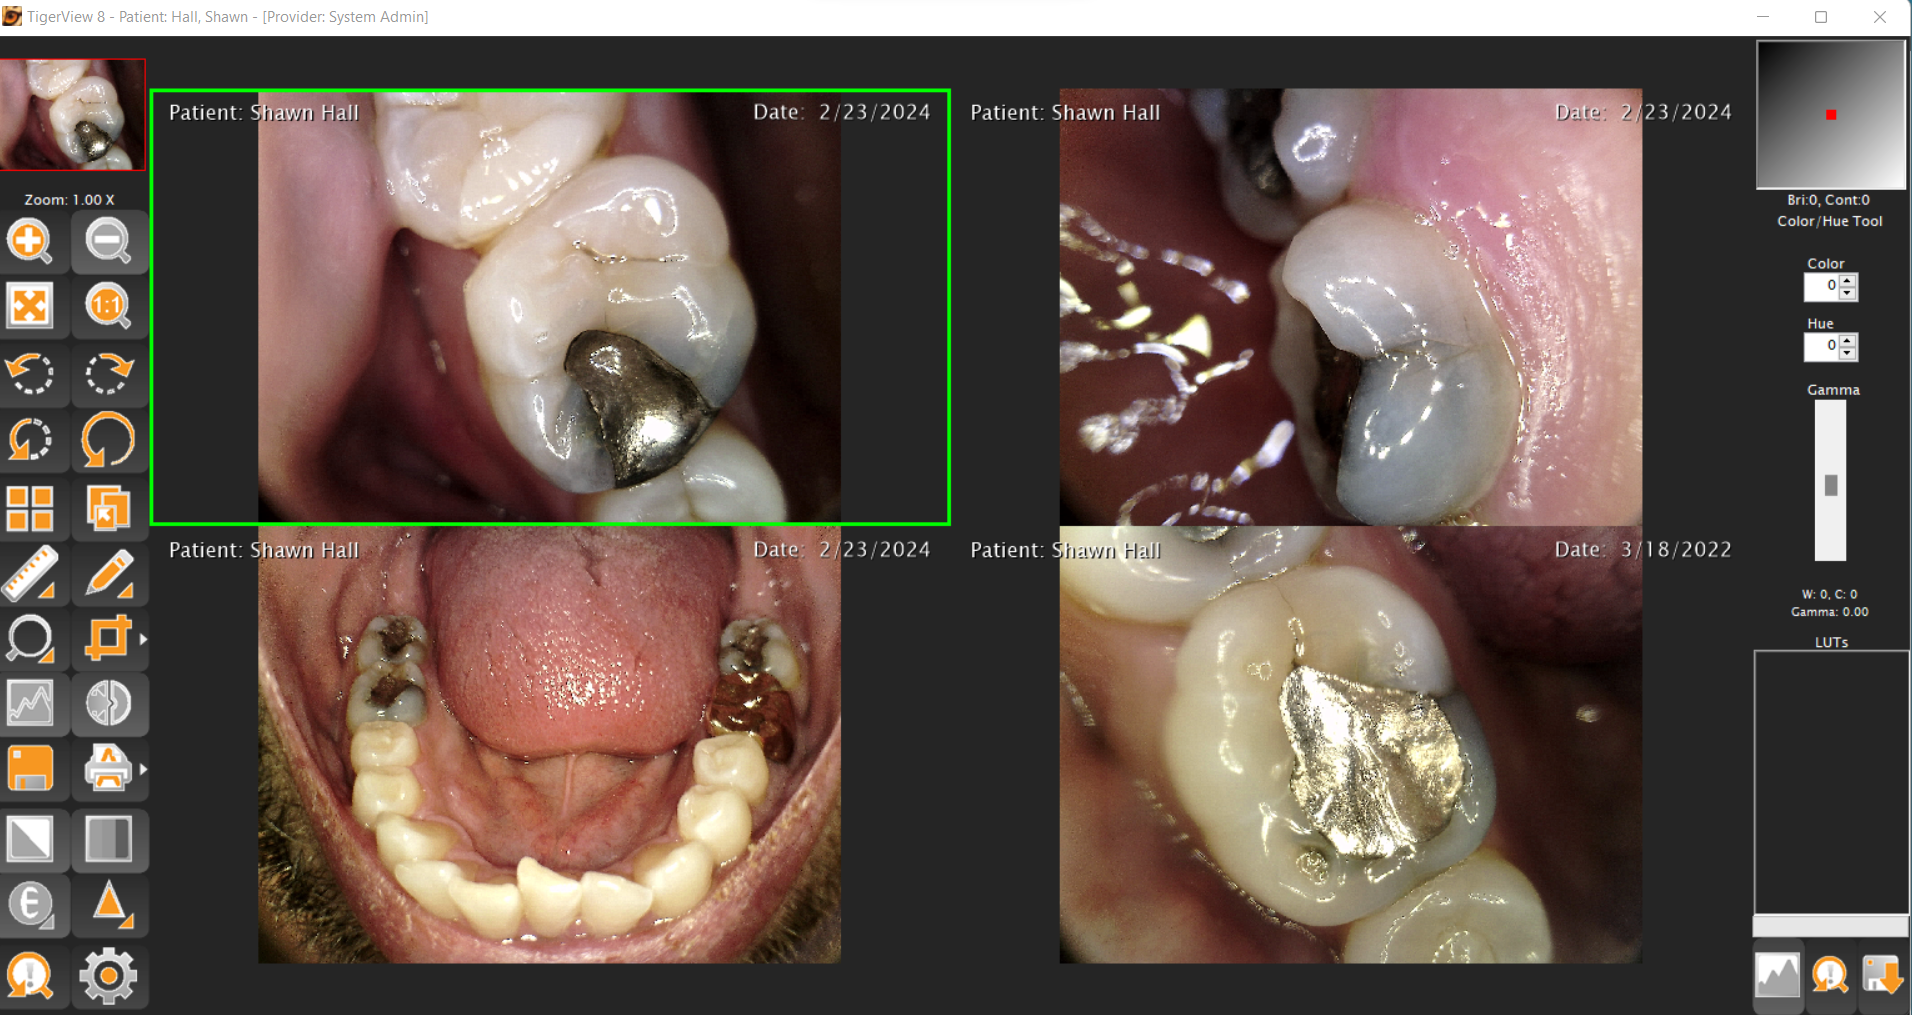

The TigerView Imaging Base Package is the foundation of a modern dental imaging workflow. Designed specifically for dental practices, TigerView allows you to capture, store, view, and share all diagnostic images — including digital X-rays, panoramic images, intraoral camera photos, and scanned film — from a single, unified platform.

Built with a user-friendly interface and DICOM 3.0 compliance, TigerView supports a wide range of imaging hardware from multiple manufacturers. This flexibility allows your practice to choose the equipment that fits your needs without being locked into proprietary systems. All images are stored in one database, making it easy for your team to access, compare, and present images across multiple exam rooms.